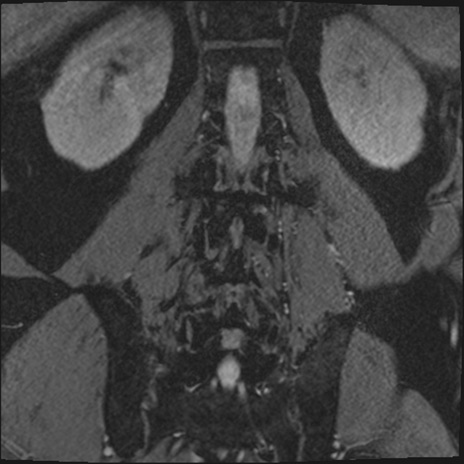

【整形】TIPS症例2 腰椎MRI 3D(冠状断像)

【症例】70歳代男性

【主訴】左下肢痛

【現病歴】2週間前くらいから腰痛、左下肢痛あり。左臀部から大腿、下腿外側のしびれが常時ある。歩行とともに同部位の痛みあり。

【身体所見】Lasegue70-/60+、Bragard-/±、PTR ±/±、ATR -/-、IP 5/5、TA 5/4、TS 5/5、EHL 右第1足趾なし/3、FHL 5/5、hypersthesia(-)、足背動脈触知良好

異常所見と診断は?